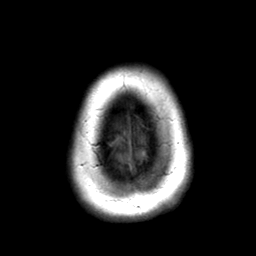

Cerebral hemorrhage, MR Study mr-t1 -- Slice #23

[Home][Help][Clinical] Slice 23